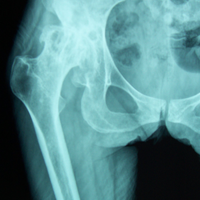

Case:3 Septic Arthritis-THR

Arthroscopy Surgeon in Ahmedabad|Spine Best doctor

2Months Pre-Op

Arthroscopy Surgeon in Ahmedabad|Sports Injuries Doctor in Ahmedabad

Imm Post-Op